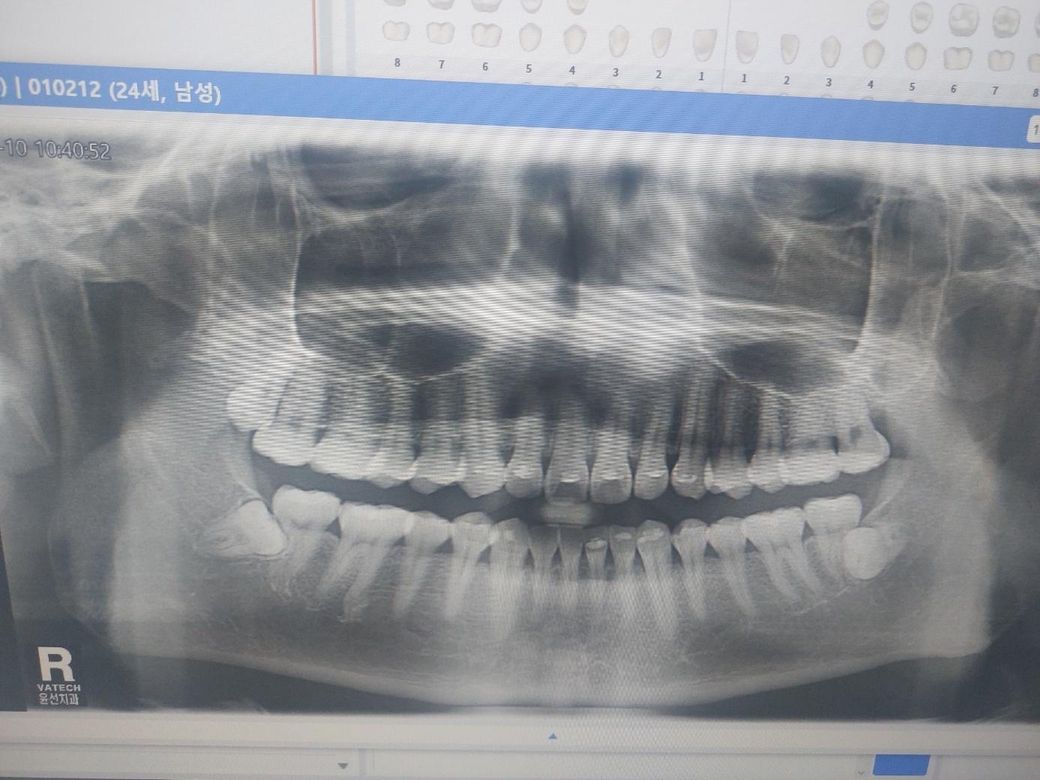

사랑니 2대구치 치근 흡수 진단좀 해주세요

하악 사랑니 2개가 어금니 뿌리를 먹고 있나요? 구강 검진 당시 그냥 사랑니 발치 해 야할거 같다고만 하고 아무 말 없었습니다 만약 치근 흡수가 되었다면 사랑니 발치하고 어금니도 못쓰나요?

해당 사진에서는 정확히 알 수는 없습니다. 해당 사진에서 정확히 보일 정도면 이미 상당히 진행된 흡수이나 현재 사진에서는 보이지 않습니다. 지금 보이는 panorama 사진은 3차원을 2차원으로 옮긴 것으로 일부 중첩되어 보일 수 있습니다. 실제로 하악 사랑니가 앞의 사랑니와 붙어 있지 않아도 지금처럼 보일 수 있으므로 dental-ct 등을 촬영하여 정확한 진단이 필요합니다.

만약 흡수가 되었다면 그렇게 될 수 있으나 위 사진은 2차원이라 씨티를 찍어봐야 알 수 있습니다.

파노라마는 단면이라 정확히 판단하기는 어렵고 CT촬영이나 발치후에 다시 확인을 해보셔야될것같습니다.

저정도면 사랑니가 옆 어금니에 아주 붙어있기 때문에 치근흡수는 이뤄졌을 것 같습니다 제2대구치를 온전히 두고 발치는 어려울 수도 있습니다